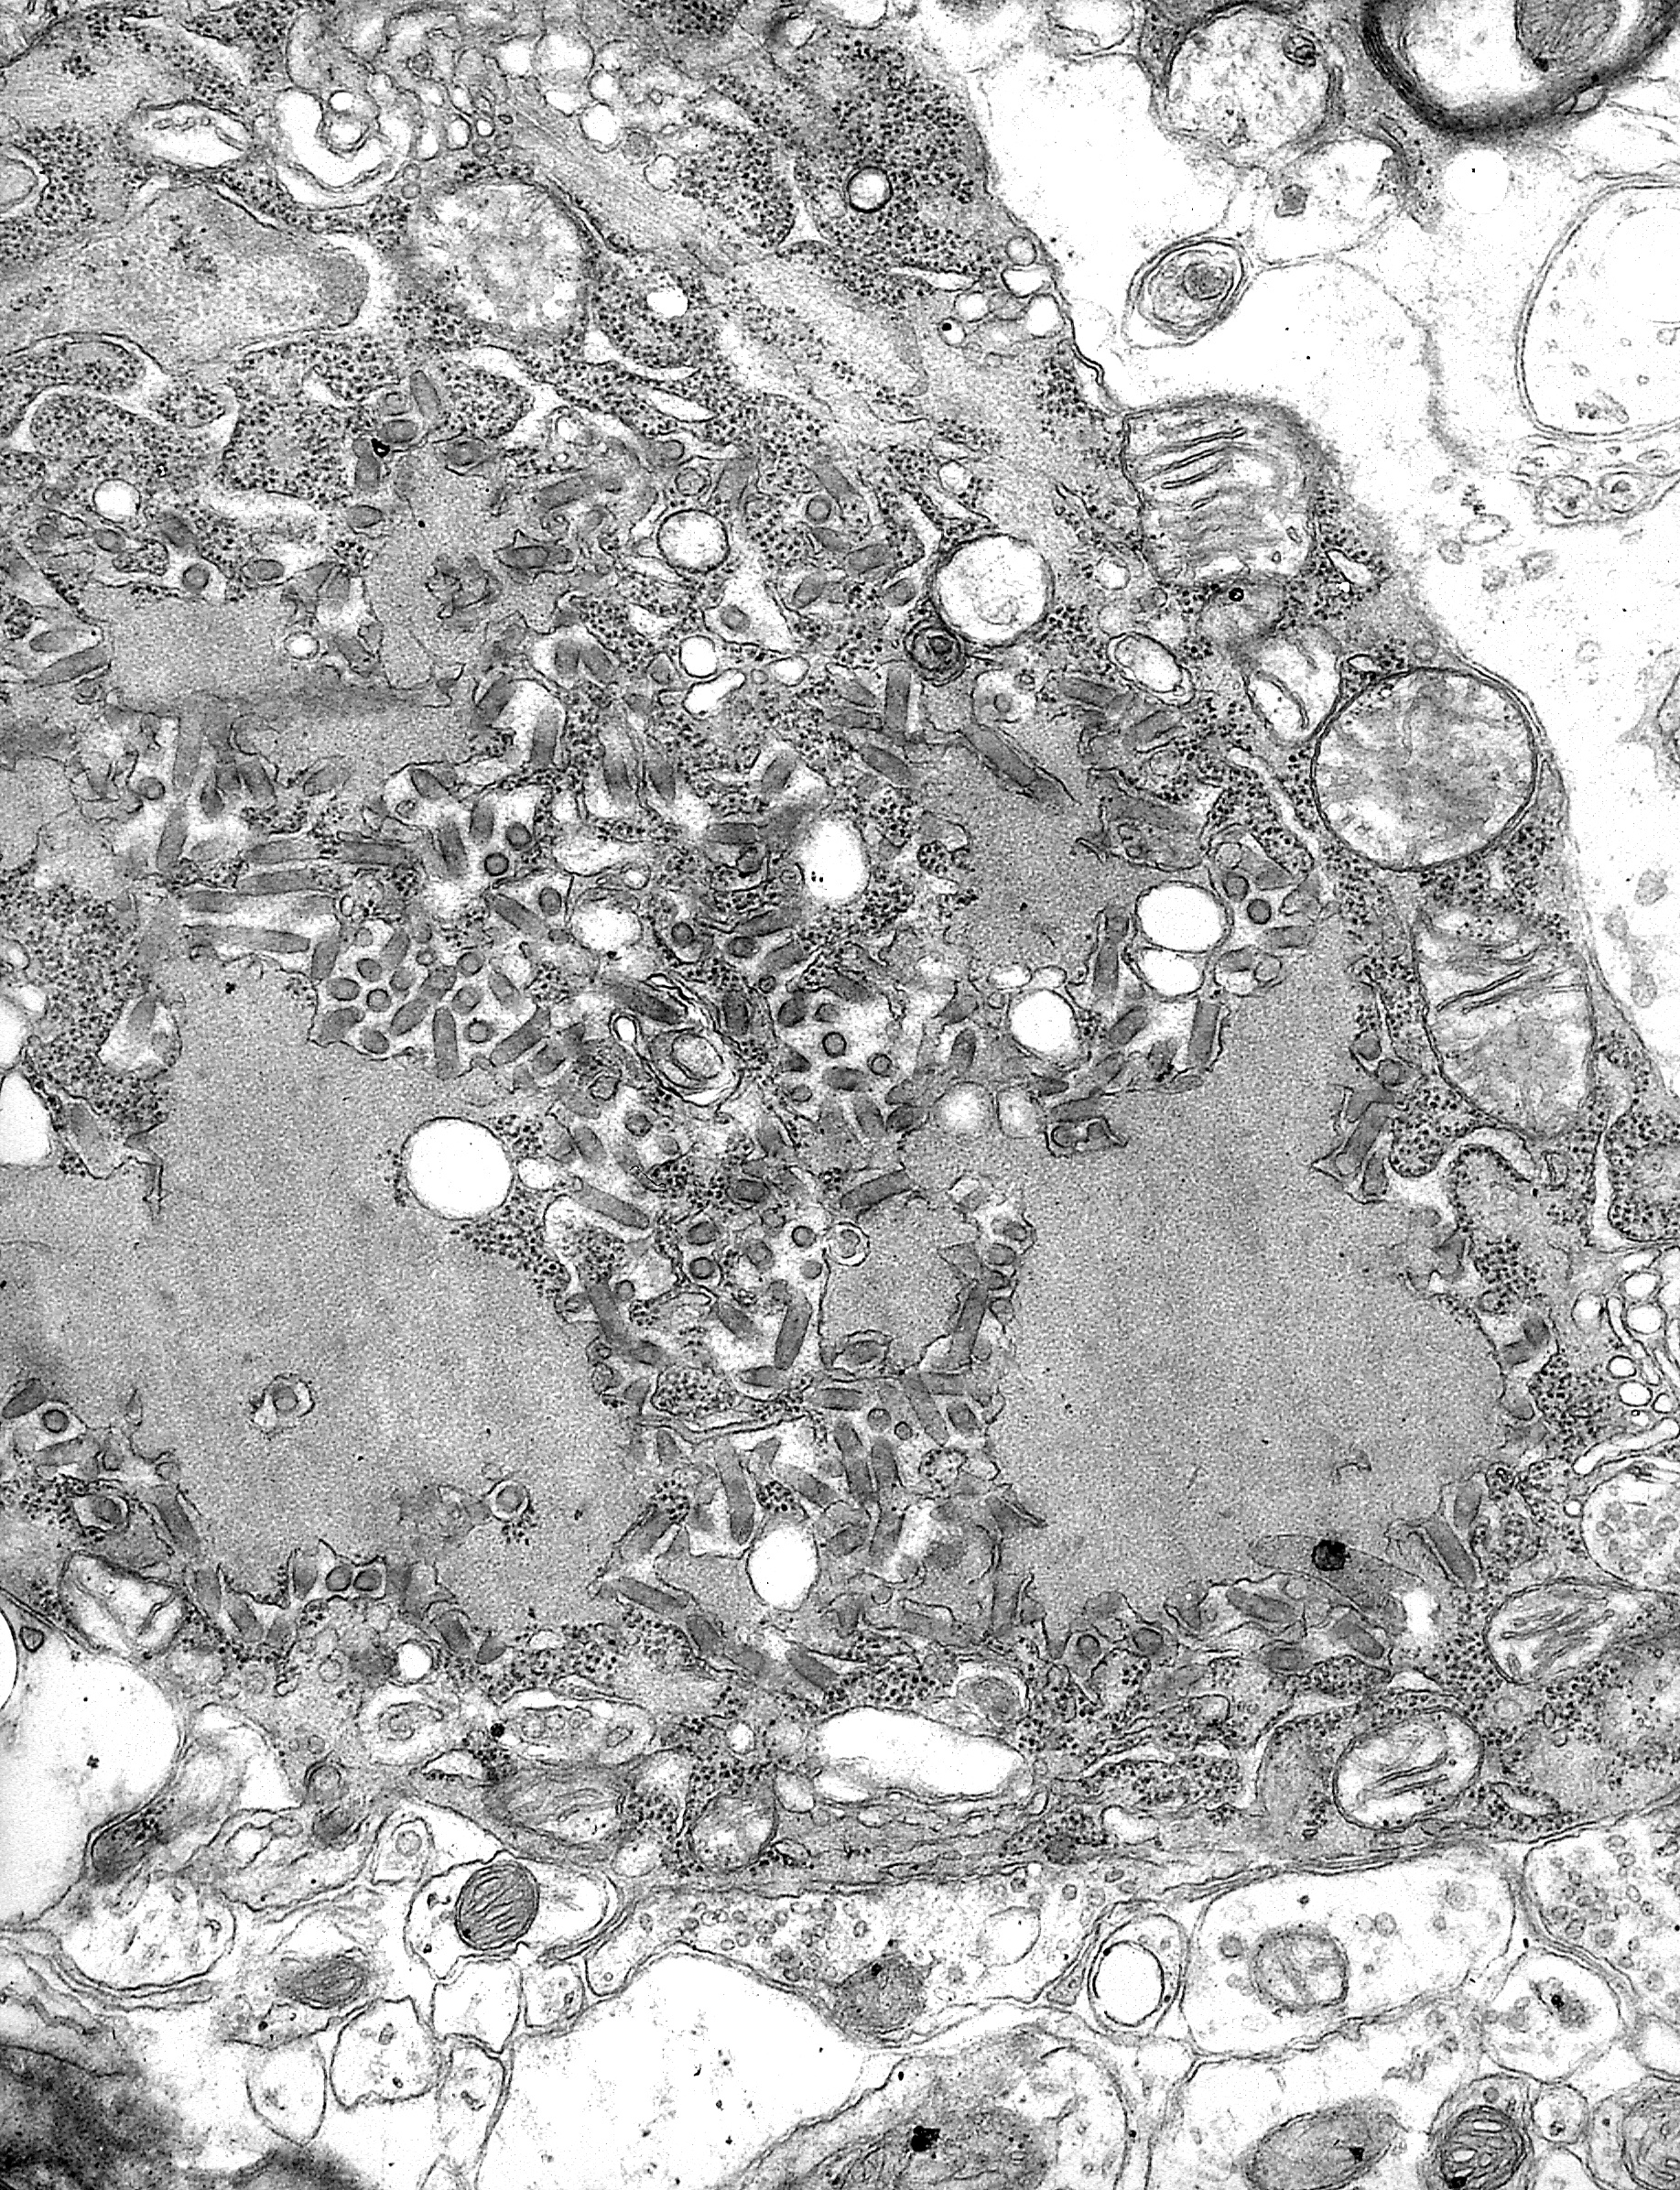

Rabies virus electron micrograph (CDC PHIL #1876)